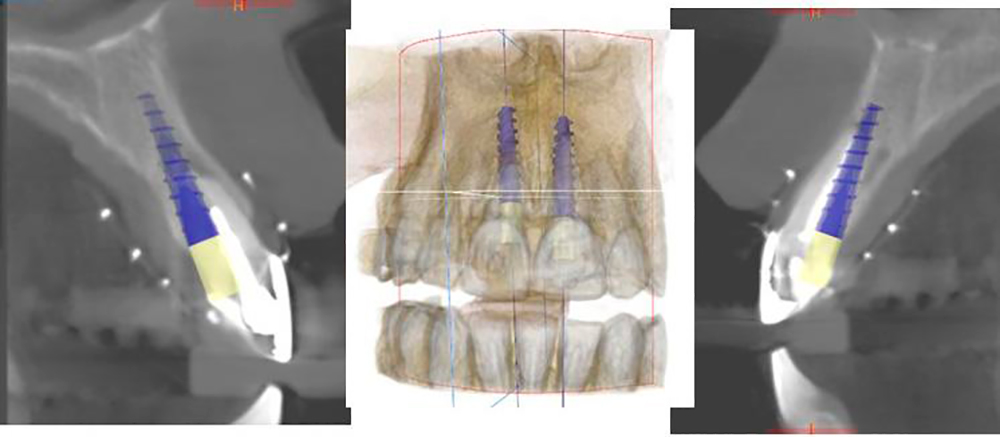

• Implantación con Guía por Mapeo Tomográfico

Socket preparation prior implant placement Using DSI DNT Drills